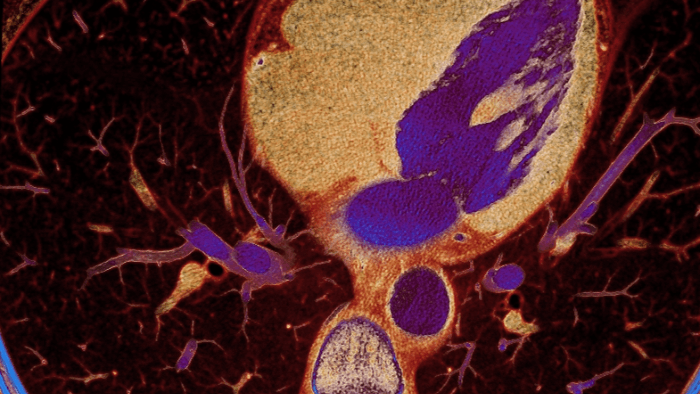

Unlike traditional CT images, spectral-detector CT images capture spectral information 100% of the time —without special planning or set-up. That means you can analyze the spectral data in any image retrospectively, using a variety of spectral viewing tools. You can, for example, adjust the monoenergetic level or get Zeffective maps.

How spectral detector works

Spectral detector simultaneously absorbs and differentiates high and low energy from a single polyenergetic X-ray beam. Spectral results are acquired within a single scan without the need for special modes.

Detector-based spectral CT simultaneously absorbs high and low energies in the same time and space.